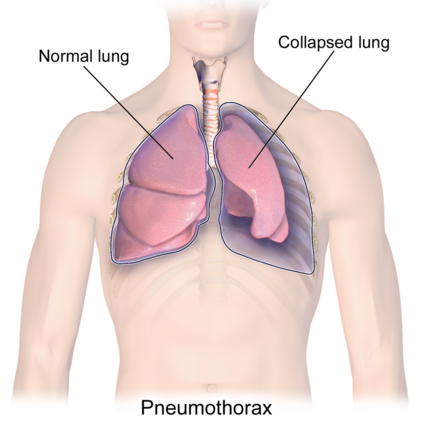

Computer-aided diagnosis for medical imaging is a well-studied field that aims to provide real-time decision support systems for physicians. These systems attempt to detect and diagnose a plethora of medical conditions across a variety of image diagnostic technologies including ultrasound, x-ray, MRI, and CT. When designing AI models for these systems, we are often limited by little training data, and for rare medical conditions, positive examples are difficult to obtain. These issues often cause models to perform poorly, so we needed a way to design an AI model in light of these limitations. Thus, our approach was to incorporate expert domain knowledge into the design of an AI model. We conducted two qualitative think-aloud studies with doctors trained in the interpretation of lung ultrasound diagnosis to extract relevant domain knowledge for the condition Pneumothorax. We extracted knowledge of key features and procedures used to make a diagnosis. With this knowledge, we employed knowledge engineering concepts to make recommendations for an AI model design to automatically diagnose Pneumothorax.

翻译:医学成像的计算机辅助诊断是一个研究周全的领域,目的是为医生提供实时决策支持系统。这些系统试图检测和诊断各种图像诊断技术,包括超声波、X光、MRI和CT等多种医疗条件。在为这些系统设计AI模型时,我们往往受到很少的培训数据的限制,对于罕见的医疗条件,很难获得积极的例子。这些问题往往导致模型运行不良,因此我们需要一种方法,根据这些局限性设计AI模型。因此,我们的方法是将专家领域知识纳入AI模型的设计中。我们与受过肺超声波诊断解释培训的医生进行了两次定性智囊研究,以获取有关肺部细胞病症的相关领域知识。我们利用这些知识获取了用于诊断的关键特征和程序的知识。我们利用这些知识,运用了知识工程概念,为用于自动诊断肺部细胞的AI模型设计提出建议。